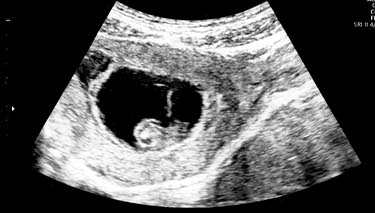

It's becoming increasingly uncommon for pregnant women to have their very first ultrasound at 20 weeks, though this used to be the first opportunity for most pregnant mums to be able to see their baby inside the uterus. It was a long wait to say the least. But now it's more common for women to be having their second ultrasound at 20 weeks gestation; the first is generally offered at around 12 weeks to screen for chromosomal abnormalities.

Another name for the 20 week ultrasound is a foetal anomaly or foetal morphology scan and it can be done anytime between 18-20 weeks of gestation. If you don t have the opportunity to have a screening ultrasound until 22 weeks of gestation, then this may be fine as well. The purpose of this scan is to assess for foetal development and growth as well as providing a means of detecting any foetal abnormalities which may relate to their structural development. In addition, their period of gestation (to see if it matches with the mother's dates), the position of the placenta and the baby's heart, lungs and organs are all checked. It is also an opportunity for parents to find out the sex (gender) of their baby. Gender prediction is fairly accurate at this stage.